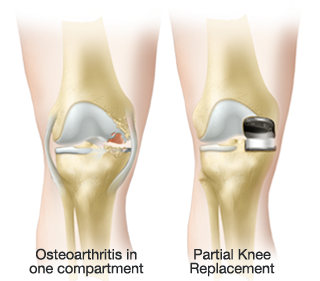

La prótesis parcial de la rodilla es una prótesis especial que está indicado en pacientes con un desgaste muy inicial y con un patrón que afecta solo un compartimiento (interno o externo) de la rodilla. La unicompartimental medial es usada para desgaste entre el fémur y tibia por dentro y la unicompartimental lateral cuando el desgaste entre el fémur y tibia es por fuera. Tiene la ventaja de resecar mucho menos hueso del paciente, así preservando más hueso para el futuro. Además, al mantener la parte biológica del cartílago y la ligamentosa de los cruzados de la rodilla, parece conservar mucho mejor la sensibilidad y la marcha de la rodilla (la propiocepción). También la recuperación de esta cirugía (al ser menos agresiva) es más rápida.

Los mejores resultados de supervivencia se ven en pacientes con poca enfermedad y poca deformidad, mayor de edad o con normo/bajo peso. Los pacientes candidatos a esta protesis probablemente no son más de 5-10% del total de pacientes con artrosis de la rodilla. No obstante, su uso general es restringido debido a la probabilidad de la progresión de a enfermedad dentro del resto de la articulación, que puede ser generador del dolor y fracaso de la prótesis, con el paso de los años. Por tanto, cuando se decide por optar por este implante precisa un consenso claro entre el cirujano y el paciente entendiendo todos los variables que puedan surgir. Siempre que se plantea colocar una protesis parcial habitualmente también se tiene preparado la protesis total por si el grado de enfermedad comprobado durante la cirugía es más de la prevista antes de la cirugía.